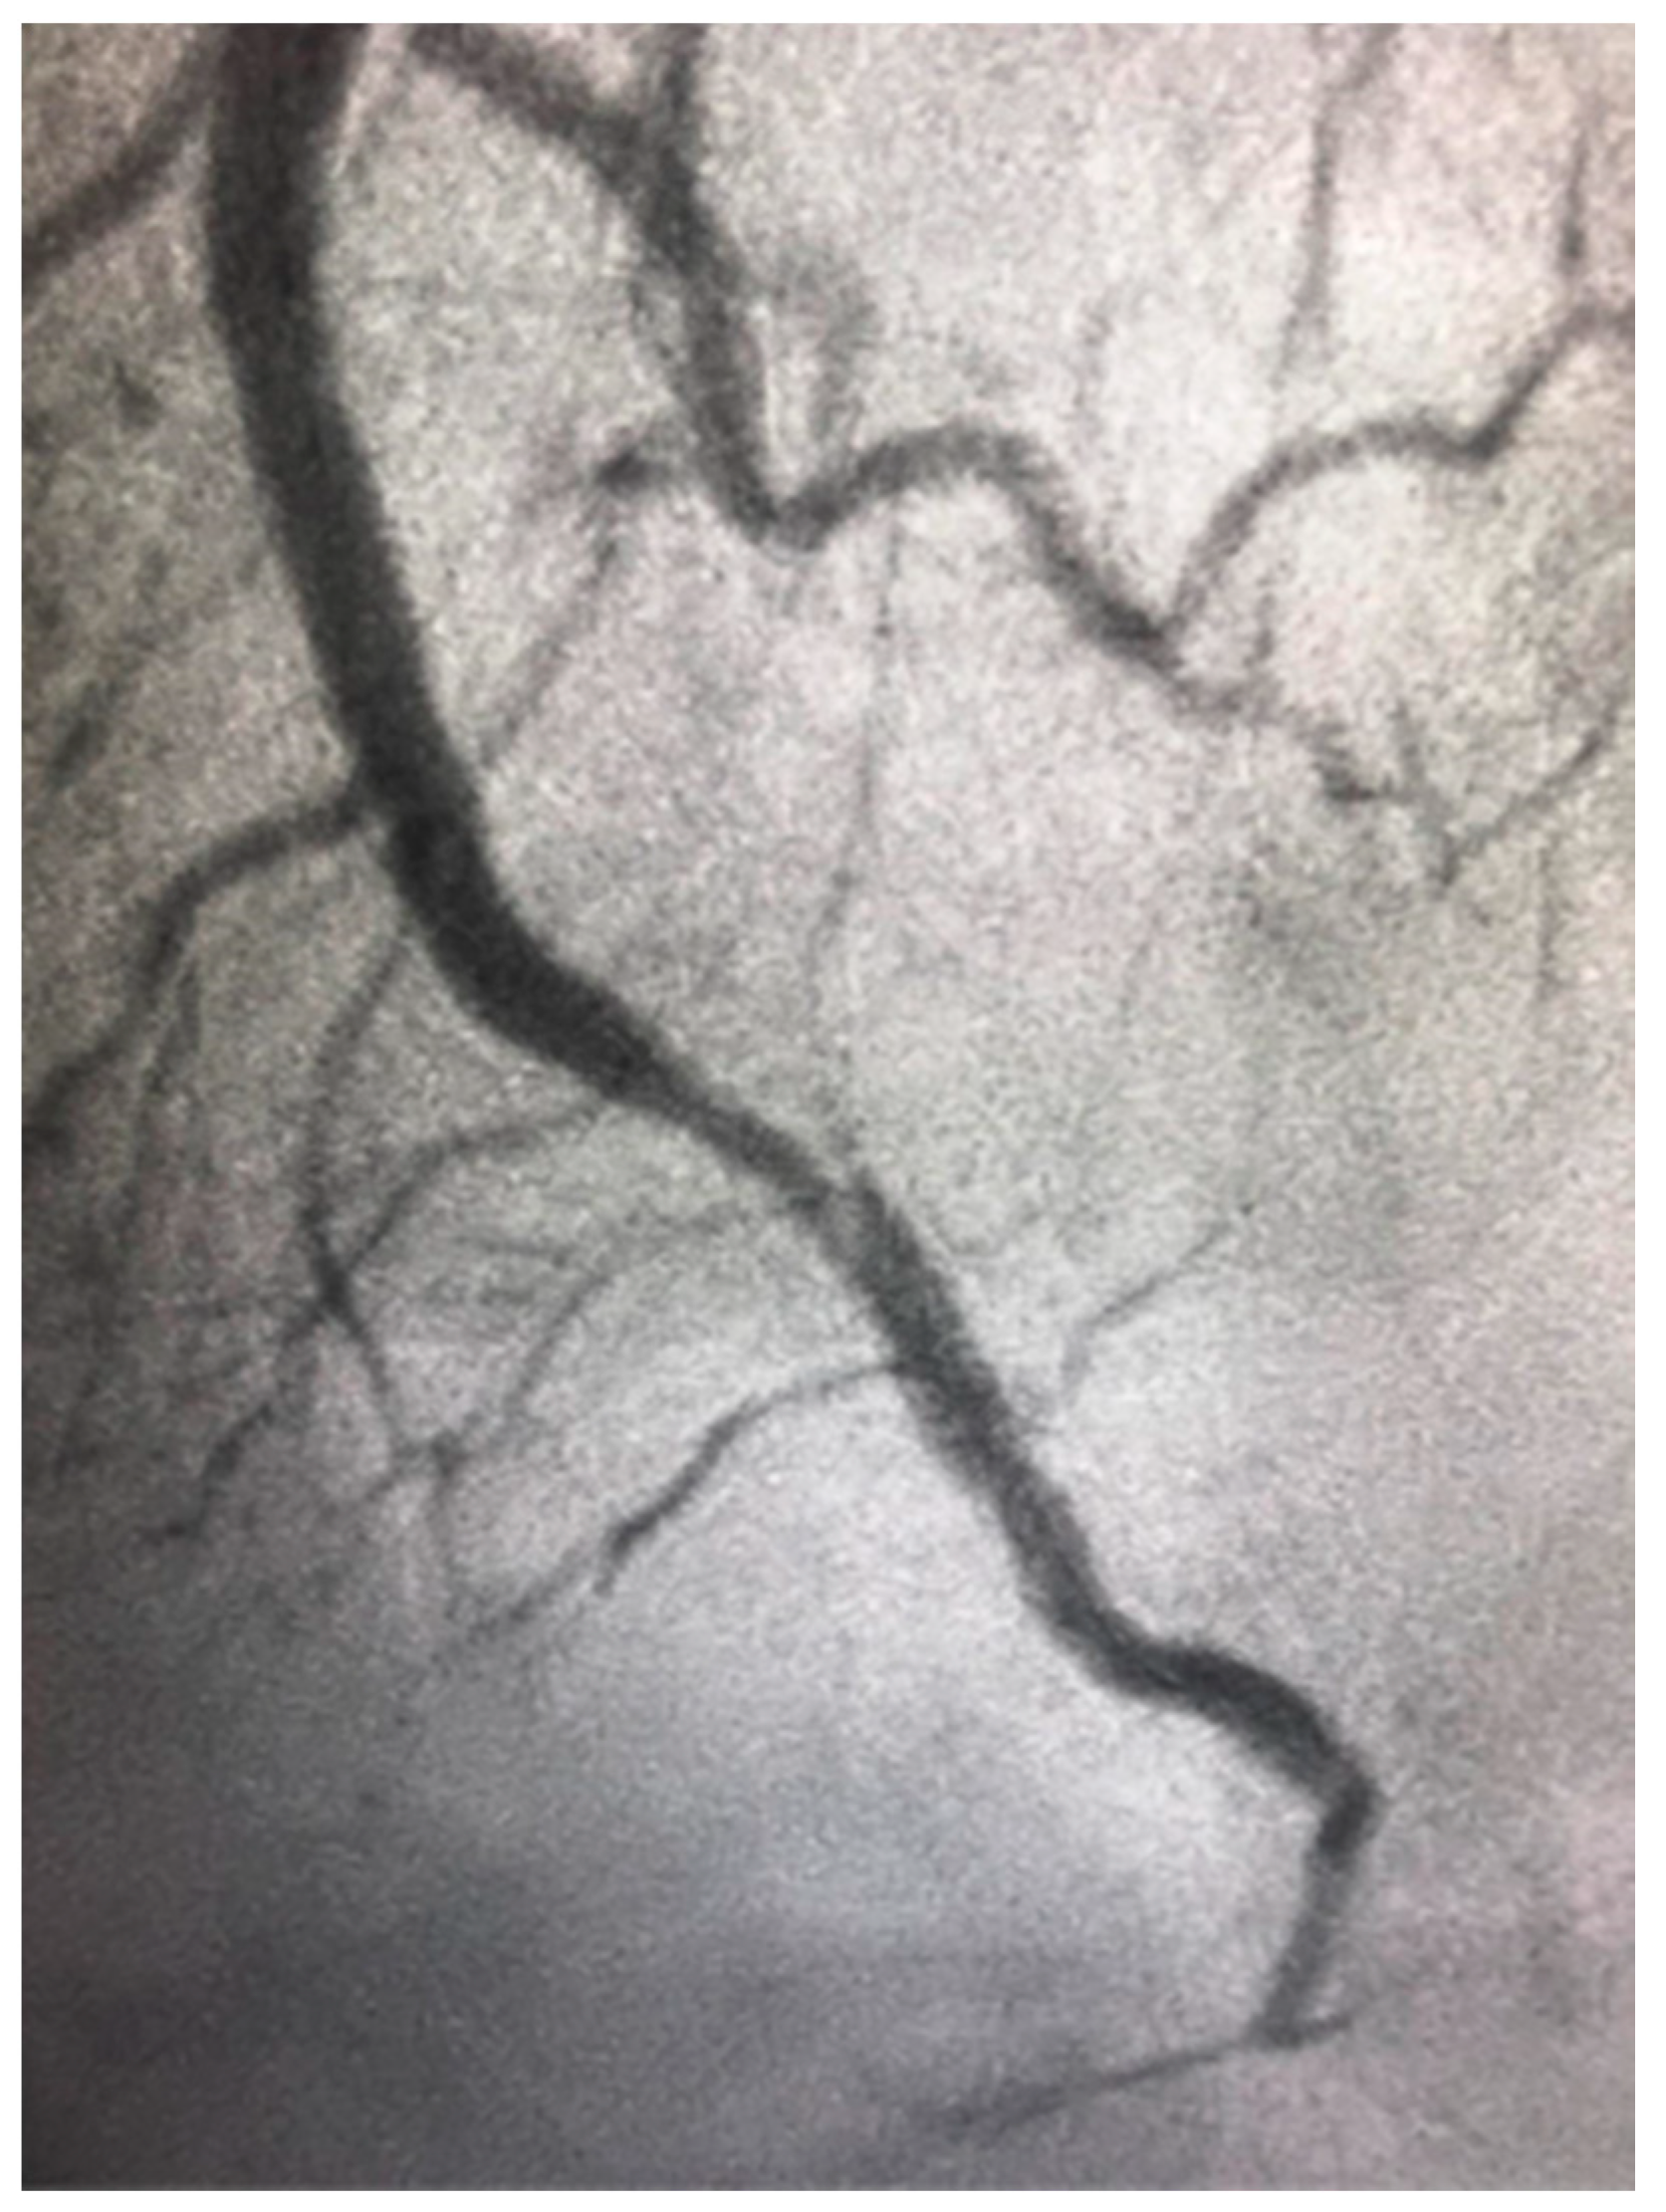

4.4. Spontaneous Coronary Artery Dissection

Spontaneous coronary artery dissection (SCAD) is due to spontaneous separation of the coronary arterial wall, creating an intramural hematoma that occludes the coronary lumen, and it is not associated with atherosclerosis (as shown in Figure 4). It overwhelmingly occurs in women. SCAD accounts for up to 4% of myocardial infarction in women and it is even more frequent among young women [67]. SCAD has a predominance in young women and is the most common cause of pregnancy-associated MI (43%) [67]. It is vital that the treating physician take SCAD into consideration when treating women with ACS. Firstly, it is associated with unique risk factors and conditions, such as a high prevalence of fibromuscular dysplasia, which need further systemic workup. Secondly, intravascular imaging should be used in some cases during coronary angiography in order to visualize the arterial wall and aid in diagnosis. Thirdly, SCAD has different therapeutic and prognostic implications compared with atherosclerotic coronary disease. It is associated with lower technical success during PCI and suboptimal outcomes, and the preferred management of SCAD is conservative in many cases [67]. Furthermore, there is an increased risk of periprocedural complications most likely because the underlying coronary artery wall is inherently weak and prone to iatrogenic dissection and propagation of SCAD with attempts to perform PCI.

Figure 4.

Spontaneous coronary artery dissection in the distal left anterior descending artery in a 46-year-old woman presenting with ST elevation myocardial infarction.